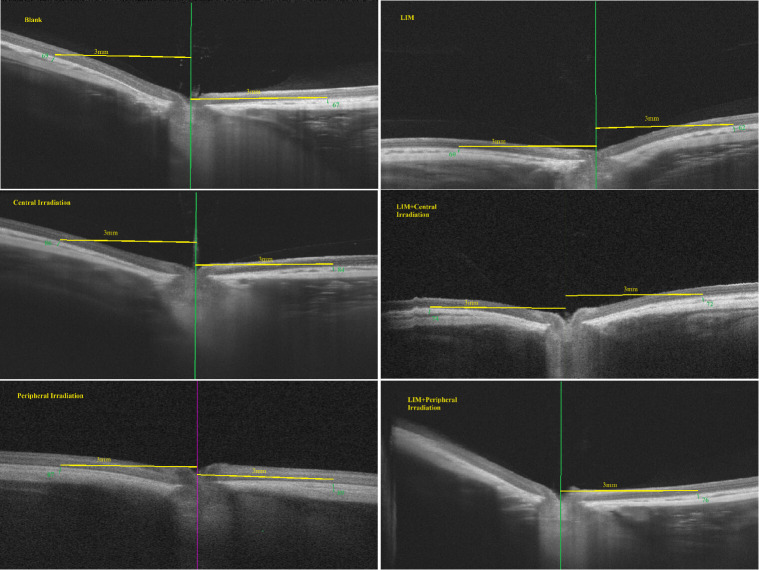

Methods: The guinea pigs (age, 2 weeks) were used. The central or peripheral retina was exposed to red light for 3 min each at 9:00 AM and 5:00 PM daily. At day 28, examinations were performed to assess the condition of axial length, the cornea and lens, and the central choroid thickness. The ratio of axial length at a given time to the baseline axial length was used to assess the axial length growth.

Results: Under the same energy density mode, illuminance (energy density) on the retina layer of peripheral irradiation is less than that of central irradiation. Under myopia induction, after 4 weeks of red light irradiation, the axial length ratios of the central and peripheral irradiation groups were 1.09±0.02 and 1.07±0.02, respectively, both significantly lower than the axial length ratio of 1.11±0.01 in the group with only myopia induction. Peripheral irradiation outperformed central irradiation in delaying axial elongation (p<0.05). Under the premise of myopia induction, peripheral irradiation but not central irradiation at 0.6 mW/cm² still delayed axial elongation. Both central and peripheral irradiation increased central choroidal thickness, with peripheral irradiation having a more pronounced effect.

Conclusion: Peripheral retinal irradiation with low-energy red light can effectively and safely slow axial growth while increasing central choroidal thickness. The follow-up period for the current study is 28 days, and the long-term safety of red light therapy for myopia necessitates further investigation.